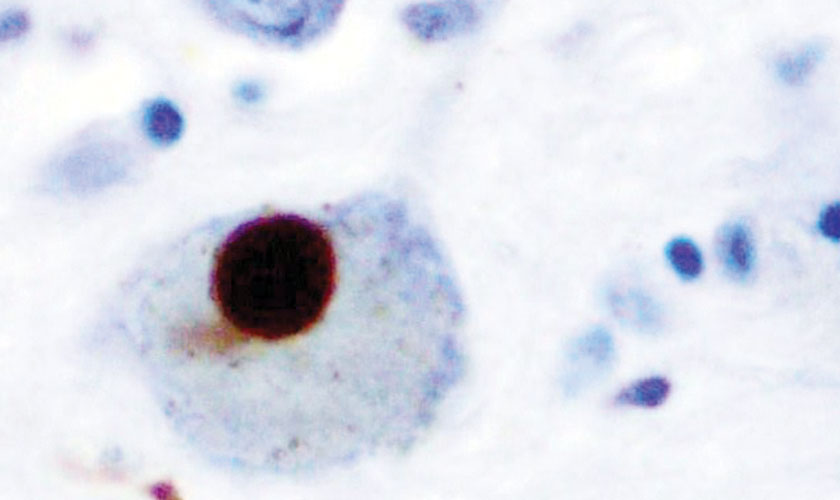

These neurons in the substantia nigra – a region in the midbrain – mainly control movement. Their loss, coupled with decreased dopamine, results in tremors (trembling in the hands, arms, legs, and jaw), rigidity (stiffness of the limbs), slowness of movement, and poor balance and coordination. These hallmark symptoms of PD appear in patients with 80 percent or greater loss of dopaminergic neurons in the substantia nigra. Lewy bodies (abnormal accumulation of alpha-synuclein proteins) develop in neurons of people with PD.